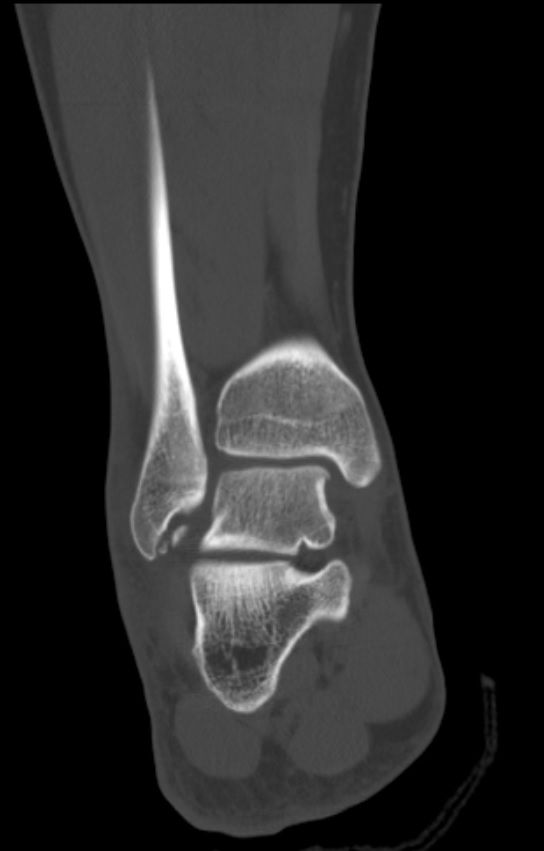

제목대로 궁금합니다 일단 통깁스하고 경과보자고 하셨는데요 이정도면 통깁스만으로도 해결 가능한정도 맞죠?? 수술할정도 아니지요??

우선 골절 정도가 뼈의 단층이 완전히 어그러진 정도로 보이진 않으나 절단면이 선명하게 보이는 정도여서 충분한 안정 후에 경과관찰 하시는 것이 좋겠습니다.

해당 CT 사진 한 컷만 놓고 이렇다 저렇다 구체적으로 판단 할 수 없습니다. 다만 해당 컷만 보았을 대에는 수술적 치료까지 필요할 정도의 골절이 보이지 않습니다.